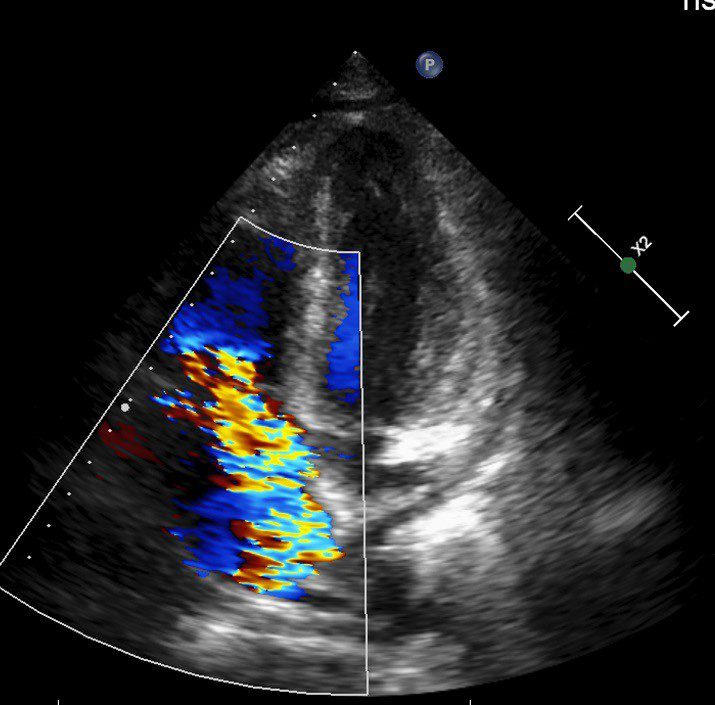

反覆發燒血球異常 三尖瓣重度逆流致脾臟腫大 20251224 2影像檢查發現三尖瓣逆流。

三尖瓣逆流並不少見,國外統計指出,有高達70%-80%的健康人群可見輕微三尖瓣逆流;但中重度以上的三尖瓣逆流發生率則較低,約占整體人口的1%-2%。大多數患者初期多無明顯症狀,直至中重度以上才會有輕微水腫出現,因此許多人往往會忽略其嚴重性,待出現嚴重問題時多已經變成重度逆流。楊凱文醫師表示:「三尖瓣逆流大多可以用藥物控制,若是進展為重度逆流且藥物治療效果不彰,同時合併右心室功能異常,就會需要手術,但臨床案例不多。」診斷上,會以超音波檢查為主,手術則會視病人狀況選擇開胸或微創手術。以林先生為例,考量病人血球數值極低、免疫力差,擔心術中出血,醫療團隊以開胸手術替其更換人工瓣膜,並同步清除感染的贅生物。